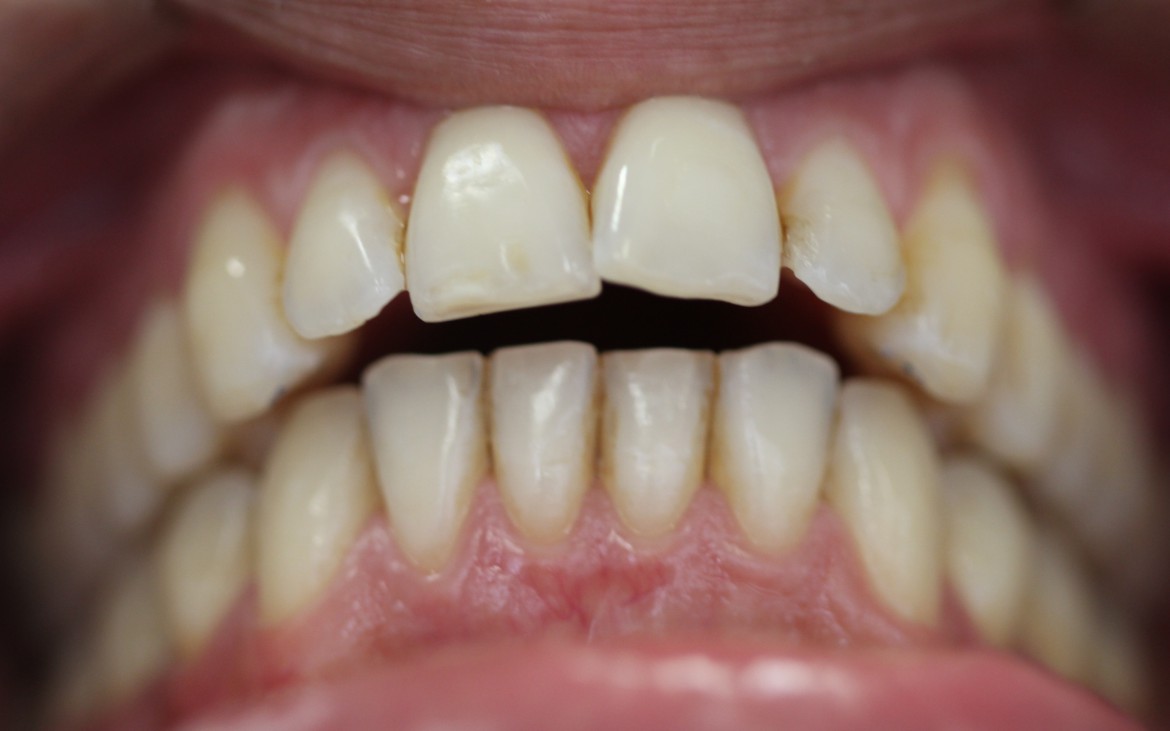

2- Oclusão classe ii de angle.

Ausência de guia anterior e guia lateral exercida em demasia pelos 1° pré-molares.

(vista lateral esquerda.)

3- Maxila e mandibula atresiadas. (Overjet anterior de 5mm).

Utilização por 18 meses de aparelho fixo auto ligável Sistema passível.

Stop na região anterior e estímulos para expansão das arcadas através de dobras offsets com fios 0.14” cuniti.